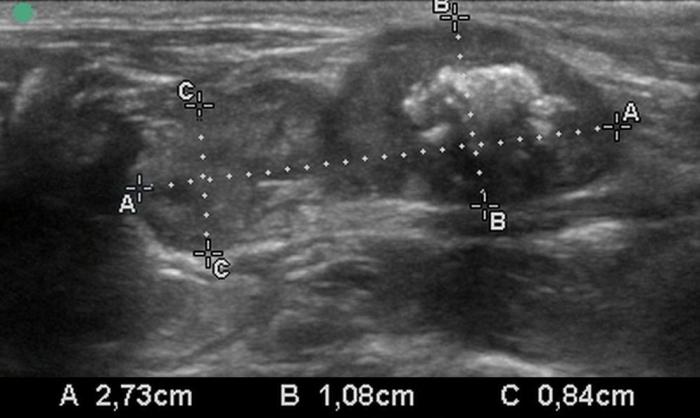

El uso de estructuras vasculares adyacentes como referencias anatómicas ha sido una estrategia útil en ecografía veterinaria para estandarizar las mediciones de órganos pequeños como la glándula tiroides. En este contexto, Bandula Kumara et al. (2019) propusieron la medición de la relación entre el diámetro tiroideo (TD) y el diámetro de la arteria carótida común (CCA) como una forma práctica de evaluar el tamaño de la glándula en perros clínicamente normales (Figura 5A-B).

Los autores realizaron un estudio en el que midieron el diámetro anteroposterior de los lóbulos tiroideos y el diámetro externo de la CCA en cortes transversales obtenidos a nivel del cuello medio. Encontraron que esta relación se mantiene relativamente constante entre razas y tamaños corporales, sugiriendo que puede ser utilizada como parámetro de referencia ecográfica. Específicamente, en perros adultos sanos, la relación TD/CCA fue de 1.74 ± 0.40 (rango 1.11–2.43)6. Si los valores se encuentran por debajo del rango normal pueden ser considerados potencialmente indicativos de hipoplasia tiroidea o atrofia glandular.

Una ventaja de esta relación es que la arteria carótida común es fácilmente identificable ecográficamente, presenta un diámetro estable y poco variable en condiciones fisiológicas, y se ubica en estrecha proximidad con la glándula tiroides. Esto la convierte en una excelente estructura de referencia para normalizar mediciones entre individuos de diferente tamaño corporal, permitiendo evaluaciones objetivas en poblaciones mixtas de perros de compañía.

Además, este índice podría tener aplicación clínica en el seguimiento de animales con enfermedad tiroidea subclínica o en tratamiento, ya que permite detectar cambios discretos en el volumen glandular con buena reproducibilidad interobservador. Aunque su utilidad clínica requiere aún validación en animales con patología confirmada, representa una herramienta complementaria valiosa dentro del enfoque ecográfico sistemático de la glándula tiroides en pequeños animales.